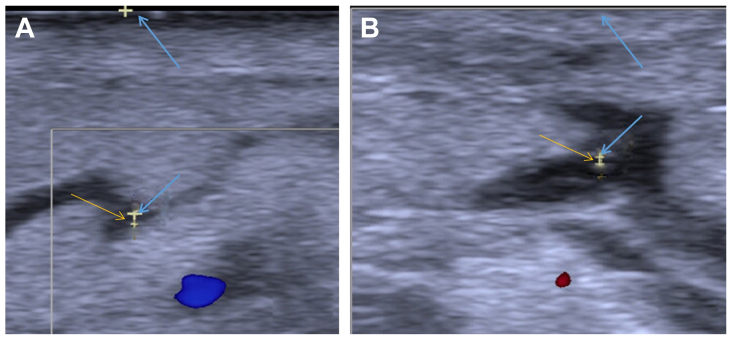

Lower limb lymphedema (LLL) is a chronic condition with impaired lymphatic drainage. Lymphaticovenular anastomosis (LVA) is a promising microsurgical treatment for LLL. Refined surgical techniques, such as optimal incision placement and precise lymphatic vessel identification, are essential for better clinical outcomes. For patients with LLL, we performed an LVA via the lymphosome-based four-incision approach. We standardized incision positioning and identified lymphatic vessels for LVA to improve surgical outcomes.

A retrospective study was conducted on 59 patients with LLL who underwent LVA. Among them, 32 patients in the study group received LVA using the four-incision approach, and 27 patients in the control group underwent LVA with empirically determined incision placement. All patients were followed up for 12 months after the operation. The outcome measures included the number of lymphatic-to-venous anastomoses, surgical duration, Lymphedema Functioning, Disability, and Health Questionnaire for Lower Limb Lymphedema and Lower Extremity Lymphedema Index, Patient Health Questionnaire-9 items, and subcutaneous thickness.